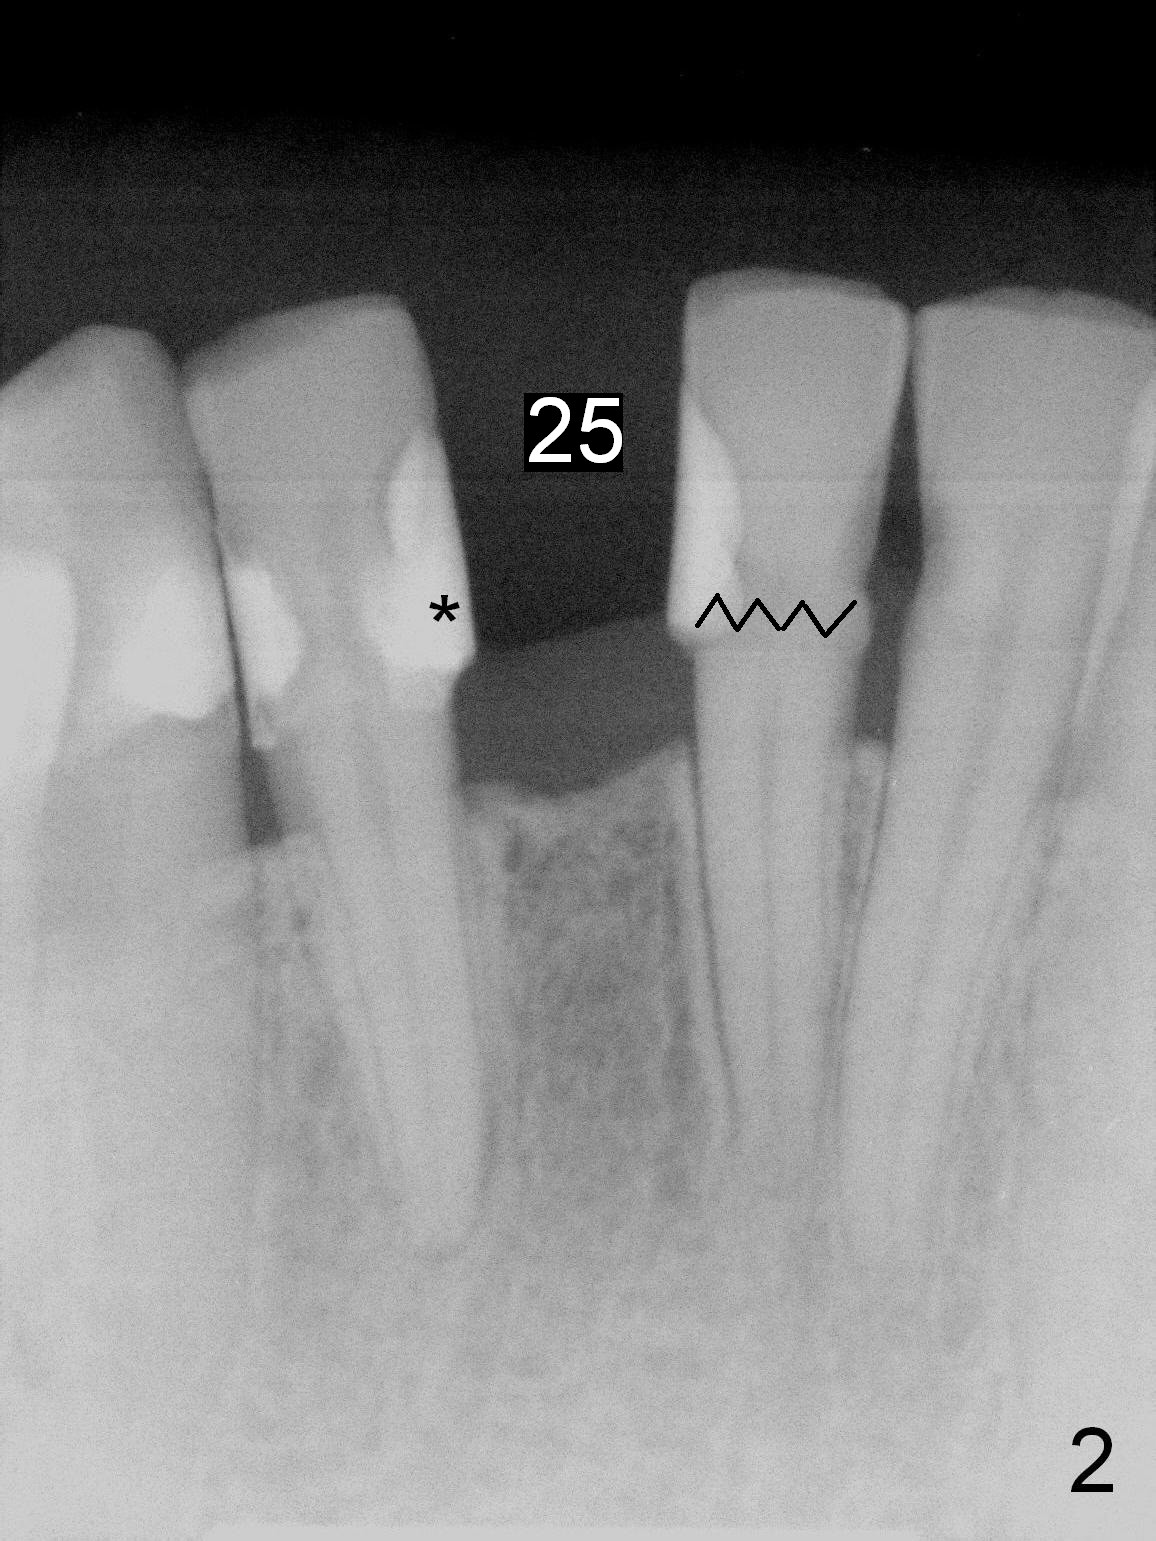

A 53-year-old woman (WX) had several missing teeth with a lower flipper (Fig.1,2, conditions 2 years ago). Recently the tooth #24 fractured equigingival (Fig.2 saw-toothed line). The edentulous area at #25 is narrow buccolingually (Fig.4a). Start osteotomy lingually (L, Fig.4b red circle). As the osteotomy increases (Fig.4c red circle) and a 2 or 2.5 mm 1-piece DIO implant is placed (Fig.4d green circle), the weaker buccal (B) plate is being expanded buccally.

A 3 or 3.5 mm 1-piece implant is placed at #24 (Fig.3) after Metronidazole socket soaking. The larger one is chosen (3.5 mm (Tatum)) if the implant at #25 fails to be placed. A dummy implant is placed partially to test trajectory. If the latter is bad, use an angled 1-piece one (Tatum). The composite overhang (Fig.2 *) is to be trimmed (Fig.3 red line). Take preop photos to show the concave buccal plate (Fig.4a) and intra- and post-op ones to show bone expansion (Fig.4b-d).